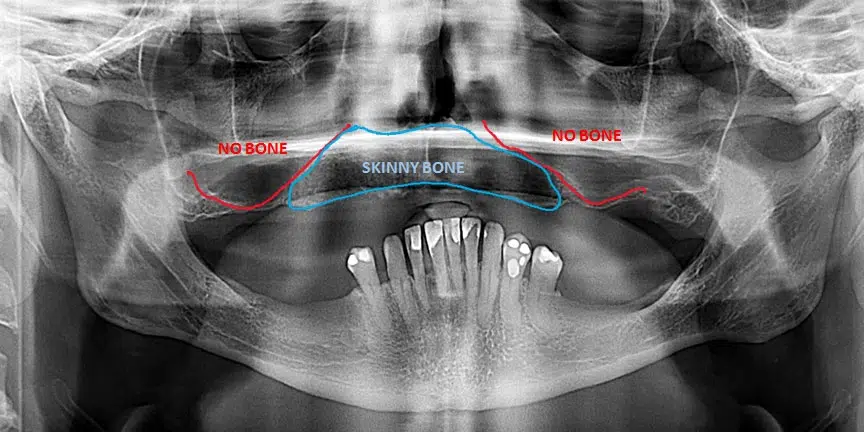

Severe Bone Loss